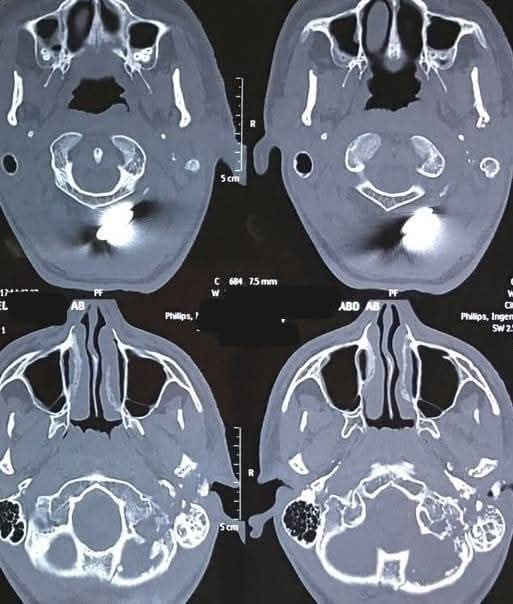

نجح فريق طبي بوحدة جراحة الوجه والفكين بمستشفى قنا العام في إجراء جراحة دقيقة لاستئصال ورم ممتد في الوجه العلوي لسيدة شابة تبلغ من العمر 26 عامًا، كانت تعاني من الورم منذ فترة طويلة، ما تسبب لها في مشكلات صحية مستمرة وتغيرات واضحة في المظهر الخارجي ...